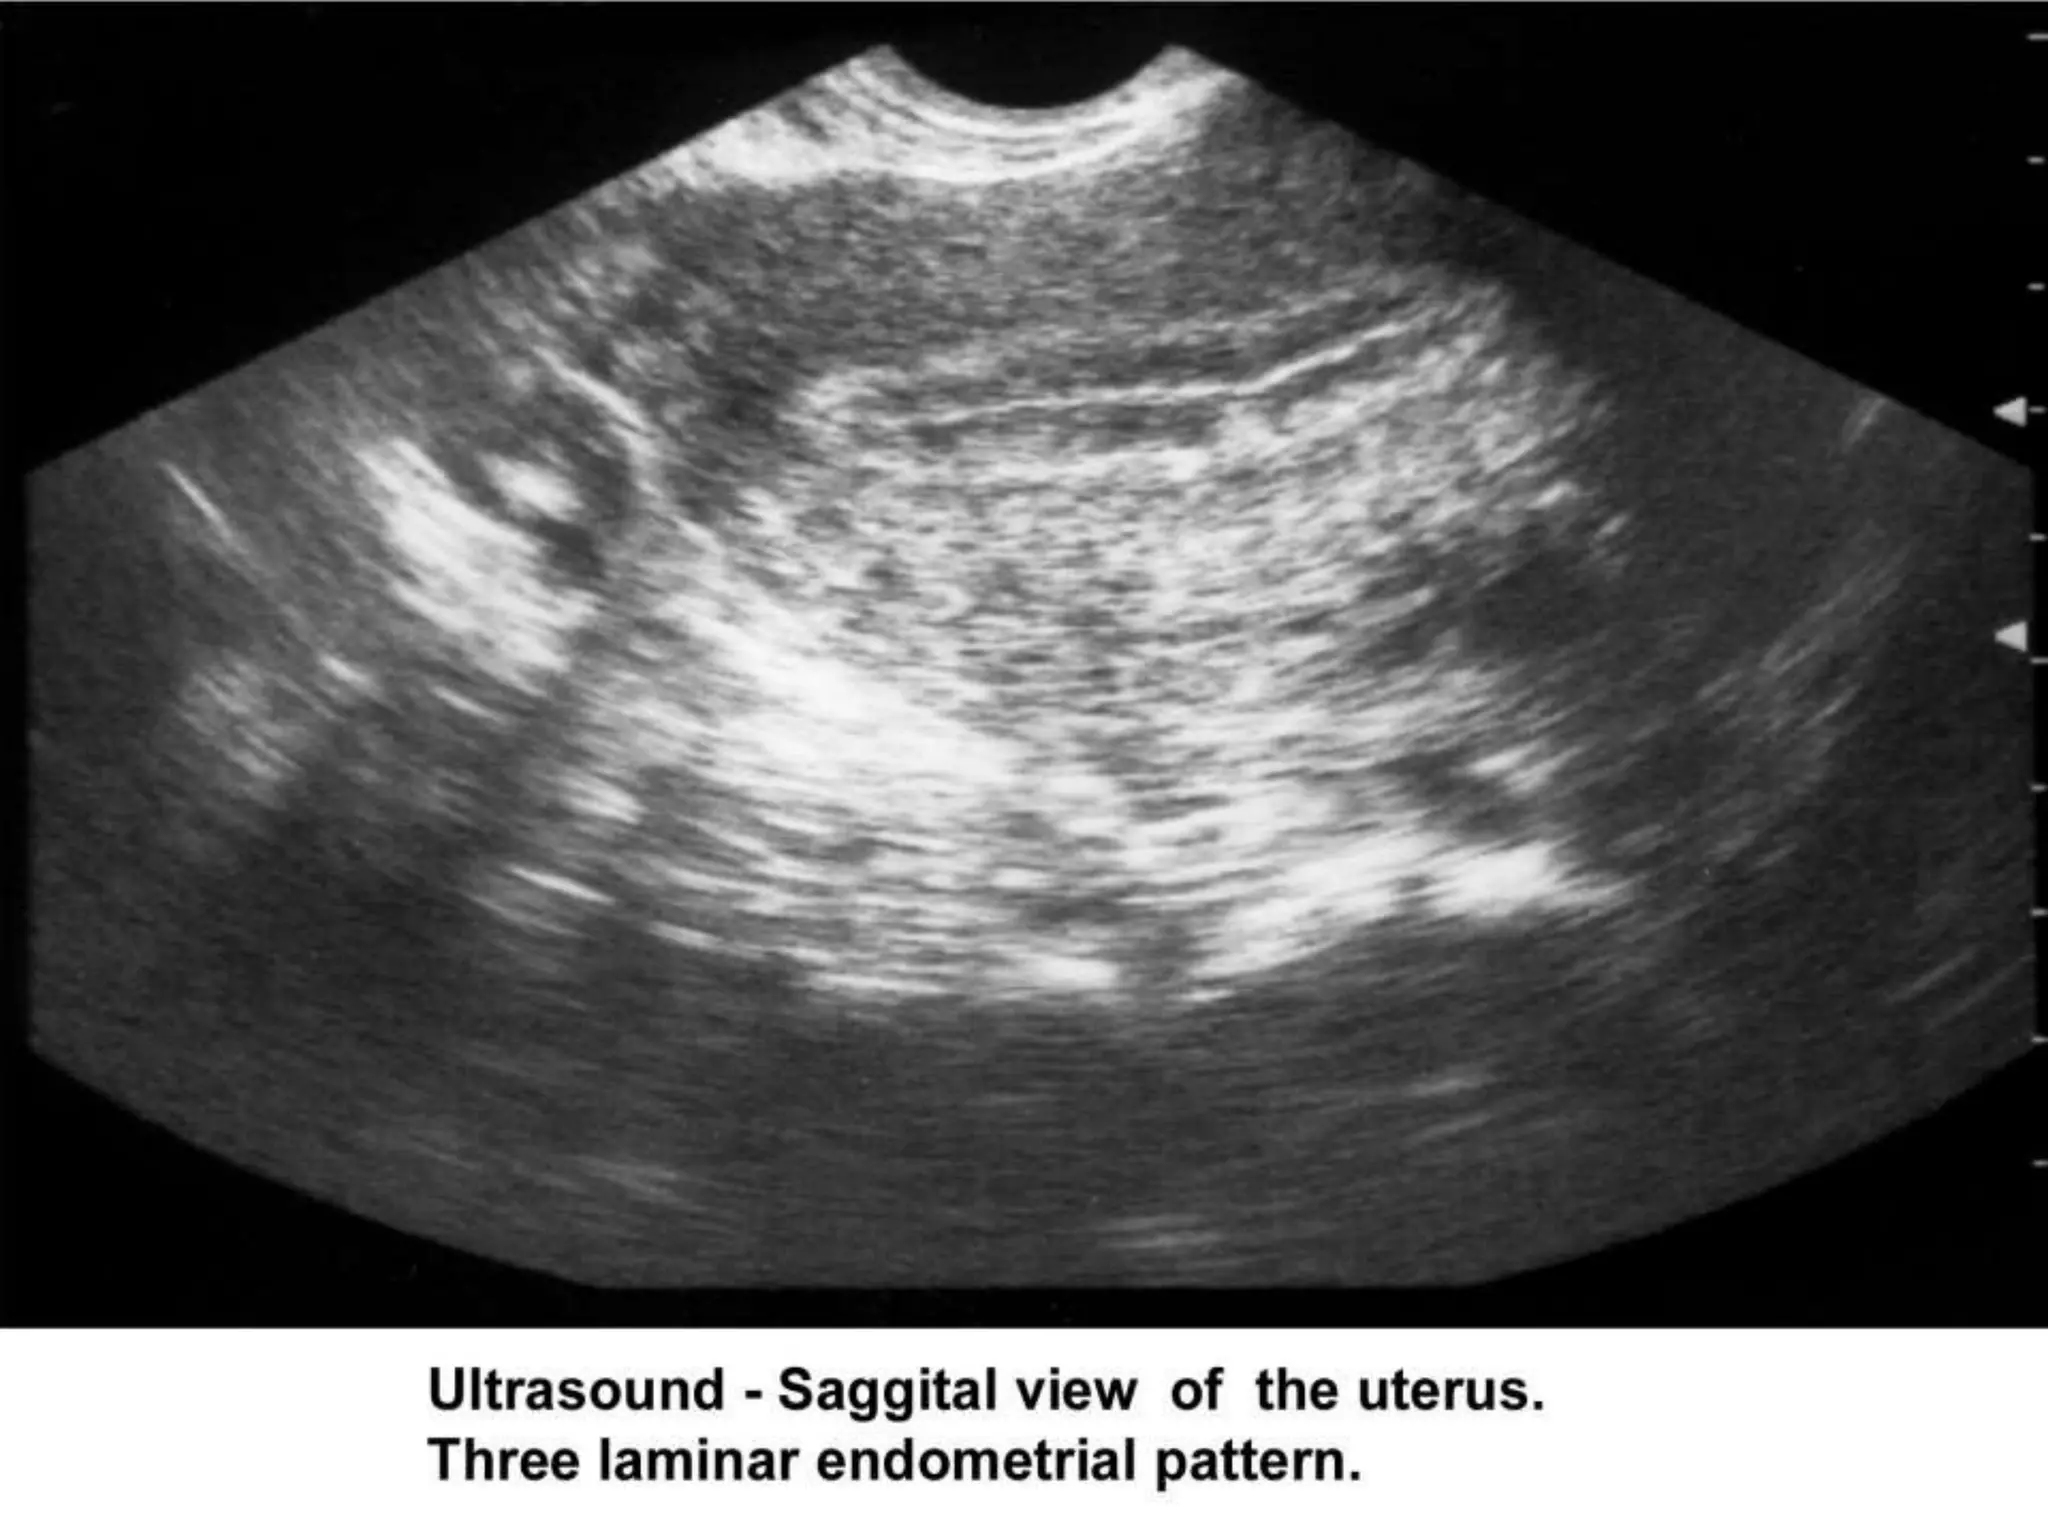

I. Ultrasonography :

 Pelvic ultrasonography should be part of the routine

gynecologic evaluation because it allows a more

precise evaluation of the position of the uterus within

the pelvis and provides more information about its

size and irregularities.

 .Pelvic sonograms also help in the early detection of

uterine fibroids, endometrial polyps, ovarian cysts,

adnexal masses, and endometriomas.

 Ultrasonography can also assist in the diagnosis of

anovulation, polycystic ovaries, and persistent

corpus luteum cysts.